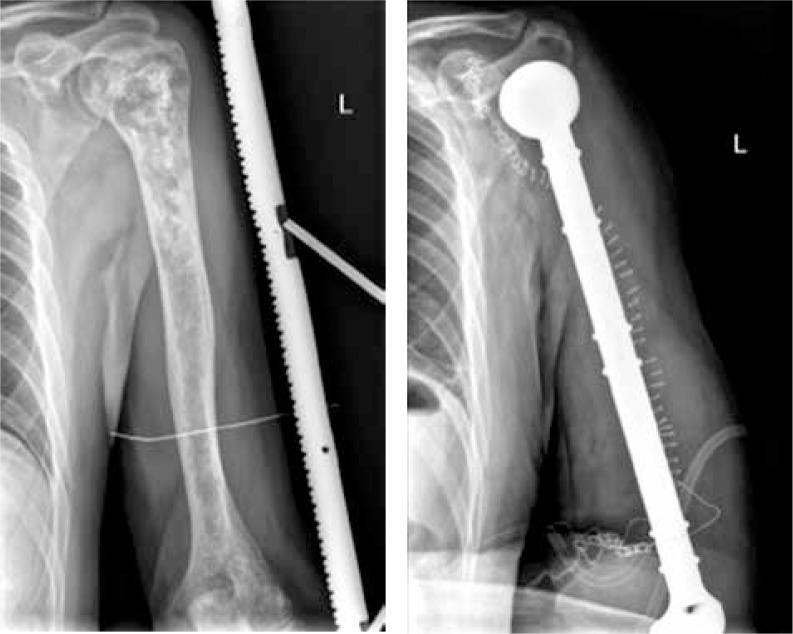

In this report, we present the results of treatment of our 11 adult patients suffering from primary bone tumours of the humerus, who have undergone wide bone resection followed by reconstruction with the use of a modular MUTARS endoprosthesis.

在本报告中,我们展示了11例患有肱骨原发性骨肿瘤的成年患者的治疗结果,这些患者均接受了广泛的骨切除,随后使用模块化MUTARS人工关节进行重建。

The study showed that prosthetic reconstruction of the resected humerus due to a primary bone tumour is safe and acceptable for patients; despite the fact that limitation of active abduction of the shoulder is up to 20 grades, this surgical procedure provides satisfactory limb function.

研究表明,因原发性骨肿瘤切除肱骨后进行假体重建对患者来说是安全且可接受的;尽管肩部主动外展受限可达20度,但该手术程序仍能提供令人满意的肢体功能。